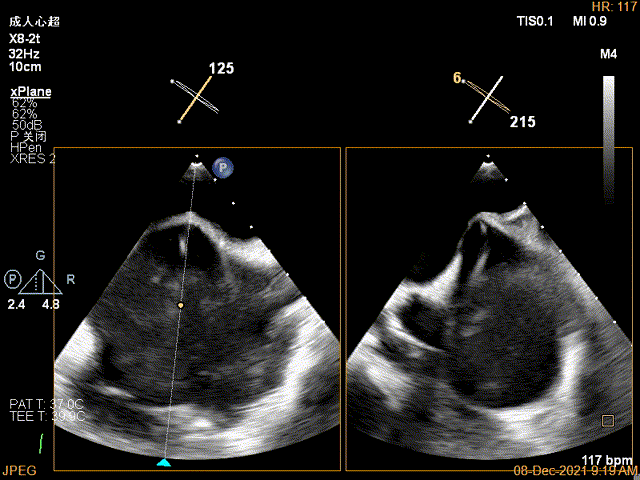

2D视图下trajectory

X-plane:下夹子尝试先捕获2区瓣叶